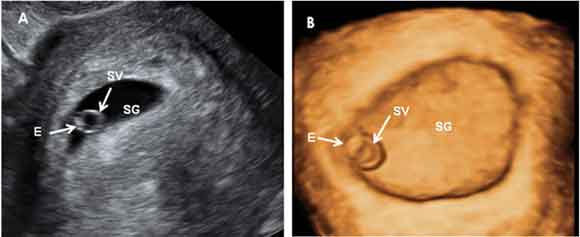

Gestación de 5 semanas en 2D y 3D

Presentamos el mismo embarazo de 5,3 semanas visto por ecografía 2D (A) y 3D (B) para que podamos apreciar las diferencias. Las siglas significan lo siguiente:

- SG: Saco gestacional

- SV: Saco vitelino

- E: Embrión, que en este caso mide de 3 milímetros de longitud